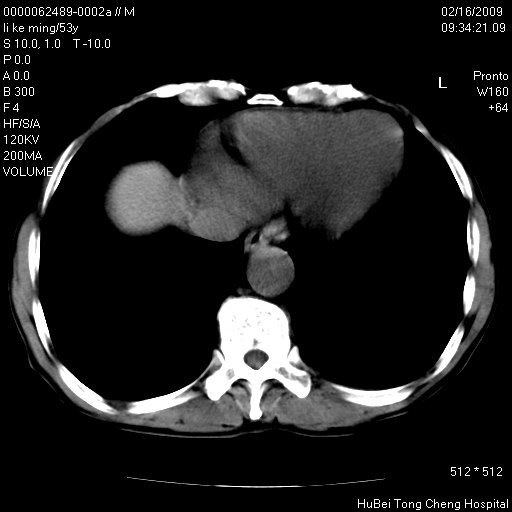

以下是引用卜一在2009-2-16 16:13:00的发言:[br]胰胆管扩张,末端明显狭窄 梗阻,胰头及十二指降段壶腹部结构紊乱。多考虑:十二指降段壶腹部癌!

以下是引用dyqct在2009-2-16 16:58:00的发言:[br]胰头内斑点状及结节状高密度影是钙化灶还是其它?以往做过什么治疗?

以下是引用zsl6918在2009-2-17 8:48:00的发言:[br]符合胰头癌侵犯十二指肠。